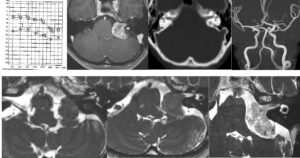

13歳小児の小脳腫瘍の摘出を行いました。術後失調や眼振が出ていましたが徐々に回復され大きな後遺症なく回復されました。よかったです。

出血の大変多い腫瘍で途中から手術に入りました。第四脳室底に癒着しておらずmedulloblastomaかと思っていましたらpilocyticでよかったです。